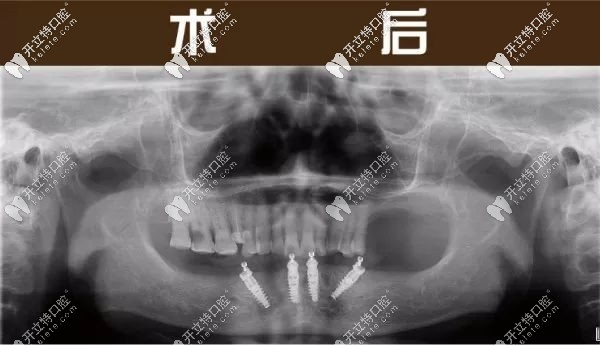

下半口做完4顆種植牙的全景片圖

(下半口做完4顆種植牙的全景片圖) ↑